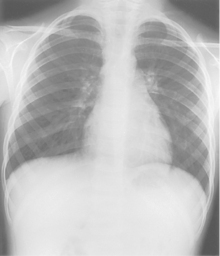

• Patient stands ≈1 ft (30 cm) away from IR, leans back against chest board

• Hands on hips, palms out, shoulders rolled forward

• Center midsternum and IR to CR, top of IR should be 3-4″ (8-10 cm) above shoulders